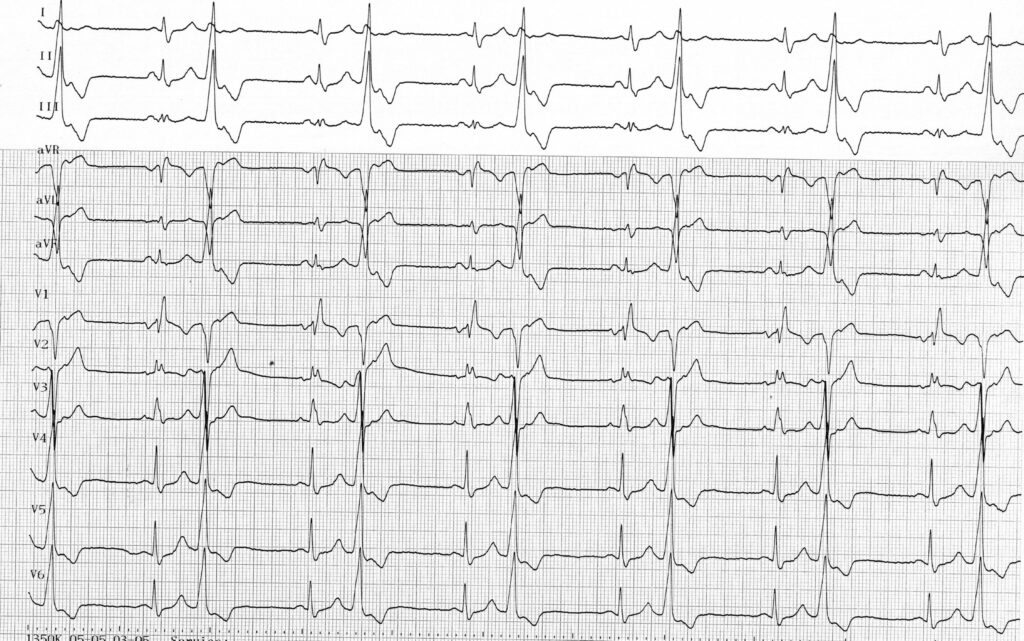

Les patients présentant des extrasystoles ventriculaires peuvent être parfaitement asymptomatiques, le diagnostic se faisant à la prise de pouls avec mise en évidence d’une irrégularité et de battements prématurés. Comme chez ce patient, la prise de pouls peut conduire au diagnostic de bradysphygmie qui correspond à un ralentissement du pouls en raison de l’inefficacité hémodynamique des extrasystoles, le pouls restant régulier si l’extrasystolie est bigéminée. Cette bradycardie effective peut entrainer une symptomatologie type asthénie ou dyspnée d’effort.

Le nombre d’extrasystoles sur une journée ne constitue pas un facteur pronostic majeur. La charge en extrasystoles est en revanche déterminante concernant l’éventuel retentissement sur la fonction cardiaque. Le bigéminisme observé chez ce patient peut, si il se maintient, être responsable du développement d’une véritable cardiopathie rythmique. La caractérisation de l’extrasystolie peut donc être complétée par la réalisation d’un Holter-ECG des 24 heures qui permet une évaluation quantitative avec mesure de la charge en extrasystoles sur 24 heures, mais également qualitative avec le nombre de morphologies différentes (extrasystoles monomorphes ou polymorphes), le couplage, l’existence de formes répétitives (présence de doublets, triplets, et/ou de salves), le lien avec la fréquence cardiaque (mécanisme catécholergique, vagal ou indéterminé), l’alternance jour-nuit (distribution nocturne et diurne). Plus que le nombre absolu d’extrasystoles, il semble que la présence d’activités répétitives à couplage très courts, permettent d’identifier les patients les plus à risque.